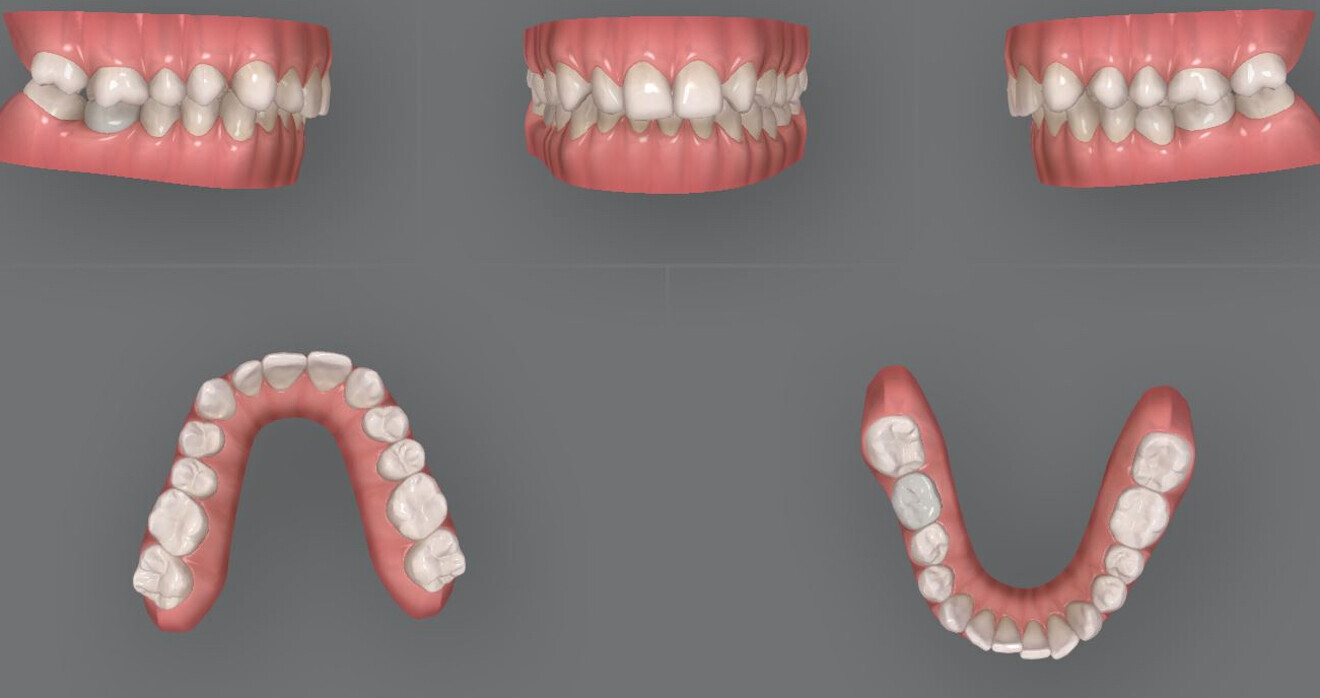

Fig. 2: Pretreatment digital models.

The patient was 32 years old when the treatment started and presented as follows (Figs. 1–3):

• missing maxillary left lateral incisor;

• Class II division I malocclusion;

• maxillary midline deviation to the left;

• mild crowding in the mandibular arch;

• Bolton discrepancy (mandibular excess of 3.06 mm in the anterior area and of 1.47 mm in total);

• long face with facial asymmetry; and

• convex profile with retruded mandible and prominent nose.

The patient had an implant in position #46, whereas teeth #16 and 26 had been endodontically treated. These teeth showed no symptoms; thus, it was decided to re-evaluate the endodontic treatments only if necessary.

The third molars were not present. The evaluation of the cephalometric radiograph (Fig. 4) showed a retrognathic mandible (SNB: 74.2°) and normal inclination of the incisors, both maxillary (Ui–FH: 111.3°) and mandibular (Li–APog: 24.2°).